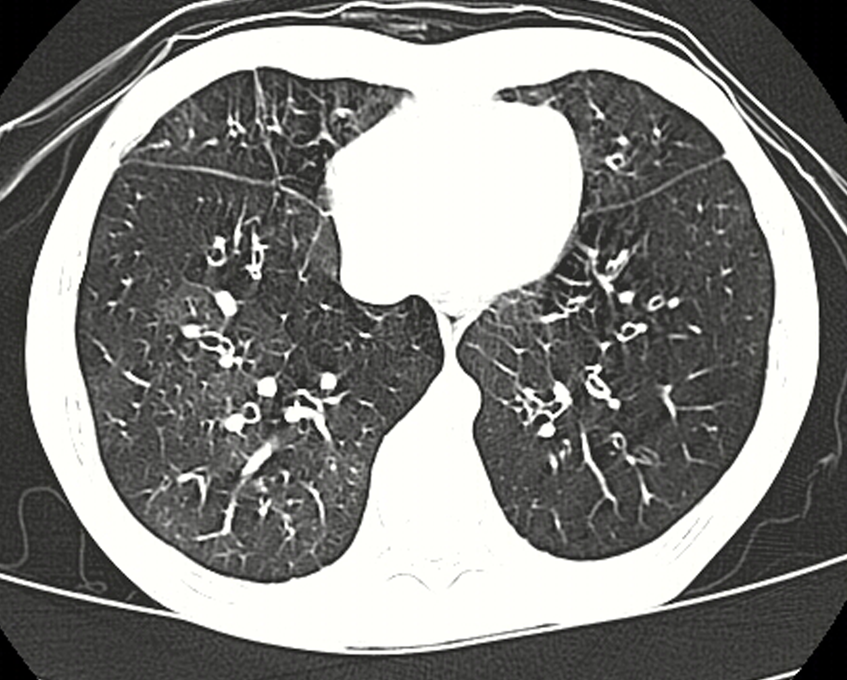

The Reports and Insights, a leading market research company, has recently releases report titled “Bronchiolitis Obliterans Syndrome Treatment Market: Global Industry Trends, Share, Size, Growth, Opportunity and Forecast 2024-2032.” The study provides a detailed analysis of the industry, including the global Bronchiolitis Obliterans Syndrome Treatment Market share, size, trends,...